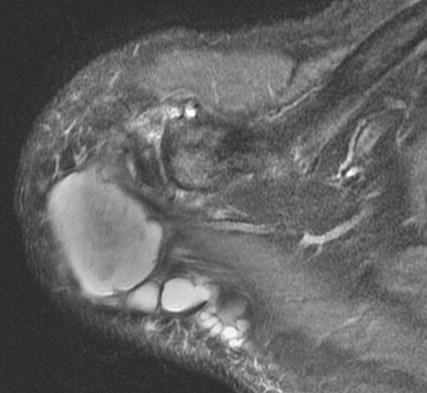

Figure 3 for case Geyser phenomenon

Figure 3